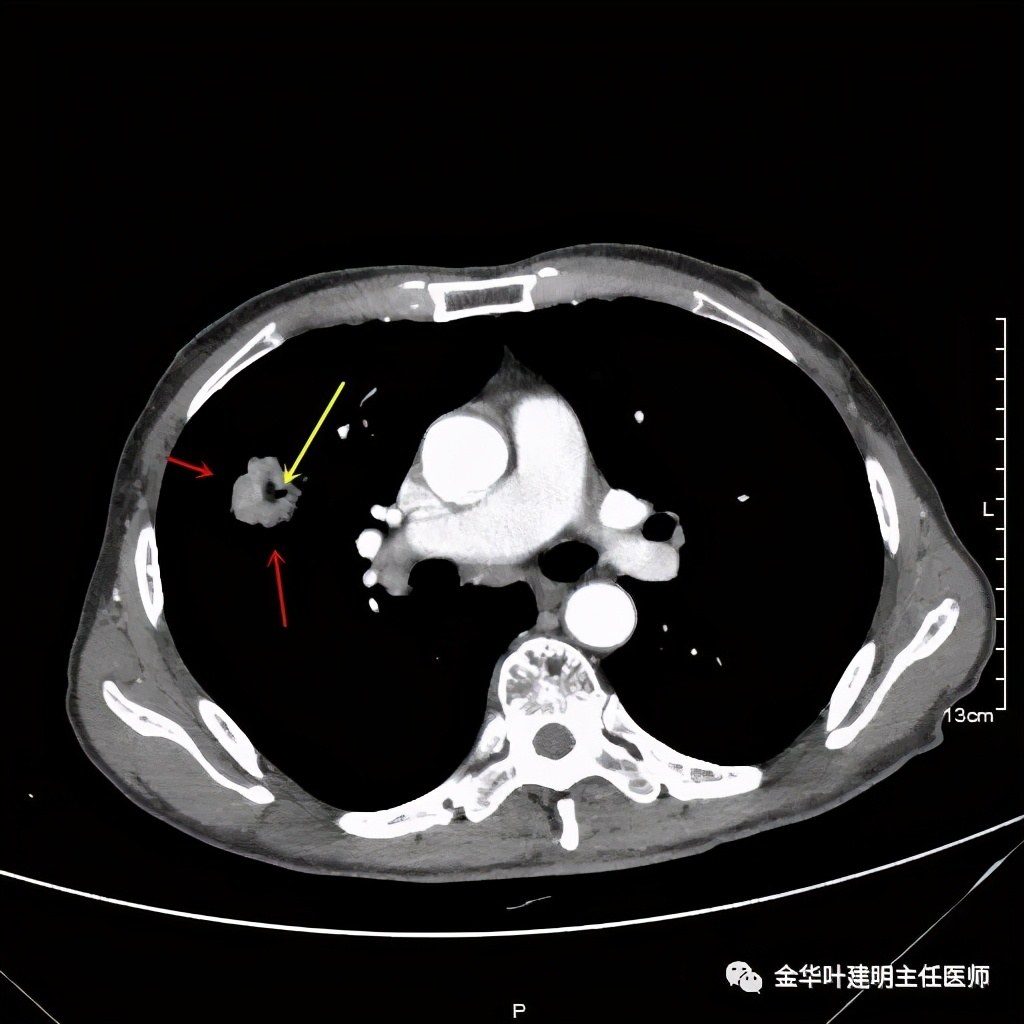

桔色箭头示病灶周围血管征明显,有较粗的血管进入病灶,较细的也有

上图箭头示强化的血管与病灶关系密切,而且有被病灶侵犯影响的感觉,部分界限是不清楚的

上图示病灶内部有条索状的强化影,考虑是病灶内的新生血管可能性大

上图也见细毛刺,但不是特别广的范围,有的边缘还是相对比较光滑了点

上图示病灶密度不均,有偏低密度的区域

上图黄色箭头示空洞形成,病灶表面不平

从影像的细节上看,有许多的影像表现是恶性的征象,这样的病灶我是认为必定恶性的,即使肺穿刺阴性!应该是假阴性,或者说,肺穿刺活检阴性并不足以让我认为它可排除肺癌,而是高度怀疑该阴性是假阴性。仍强烈建议手术切除,可以直接做肺叶切除并清扫淋巴结。患方接受了我的建议,头天刚办理出院的,次日又到我们科办理了住院手续。完善相关检查后,我们很快为其进行了“单孔胸腔镜下右上叶切除及淋巴结清扫术”,手术顺利,术后大体肉眼看就是典型的肺癌,中间坏死空洞,肿瘤质硬,收缩力强,表面不平,切面鱼肉样。术后病理确认是浸润性腺癌,下面是石蜡病理报告: